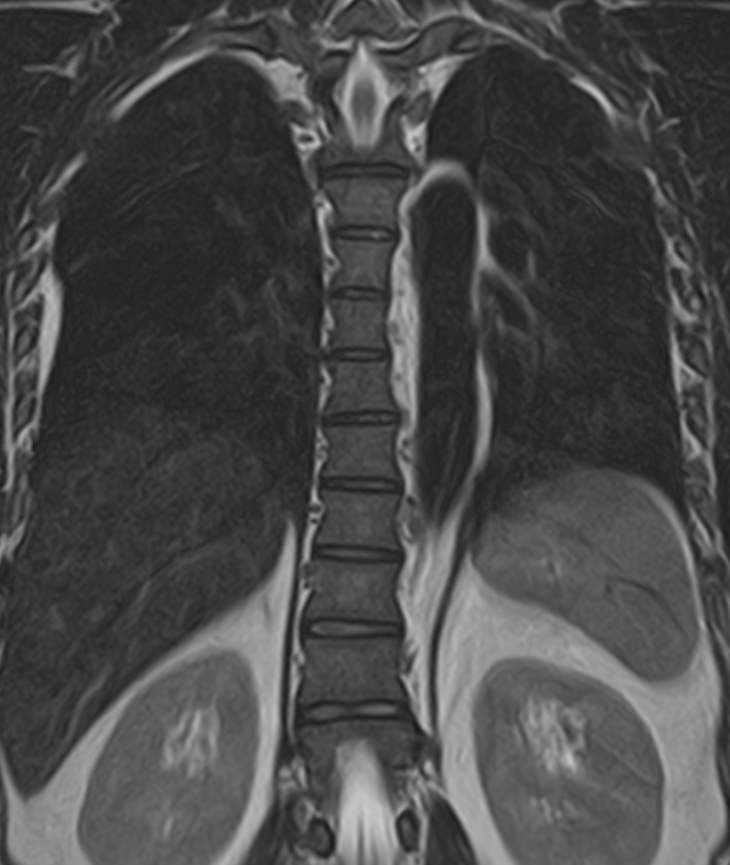

В клинике «Доступная медицина» проводится комплексное обследование позвоночника, включающее два протокола сканирования — МРТ грудного и поясничного отдела.

Магнитно-резонансная томография является наиболее точным и эффективным способом диагностики различной патологии позвоночного столба. Метод позволяет визуализировать не только костные структуры позвонков, но и оценивать состояние спинного мозга на исследуемом уровне, нервных корешков, связочного аппарата и окружающих мягких тканей. МРТ сочетает в себе высокую точность и информативность, при этом является безболезненной, неинвазивной и безопасной процедурой, так как во время исследования не применяется вредное рентгеновское излучение. В основе метода лежит использование магнитного поля, которое не оказывает негативного действия на организм человека.

Комплексное обследование грудного и поясничного отдела позвоночника обычно требуется в тех случаях, когда имеется подозрение на множественное поражение позвоночного столба, которые могут быть вызваны опухолевыми, воспалительными или дегенеративными заболеваниями позвоночника.

Магнитно-резонансная томография, предусматривающая обследование средней и нижней части спины, охватывает область семнадцати позвонков: двенадцать из них формируют заднюю стенку грудной клетки, пять находятся между ребрами и крестцовым отделом. Исследование позволяет визуализировать:

МРТ грудо-поясничного отдела позвоночника обладает высокой чувствительностью и специфичностью. Она позволяет не только определять границы патологических очагов, но и решает более сложные диагностические задачи. МР-сканирование является обоснованным методом выбора при врожденных аномалиях развития, синдроме фасеточных суставов, межпозвонковых грыжах, остеомиелите, заболеваниях спинного мозга, вертебральных опухолях.